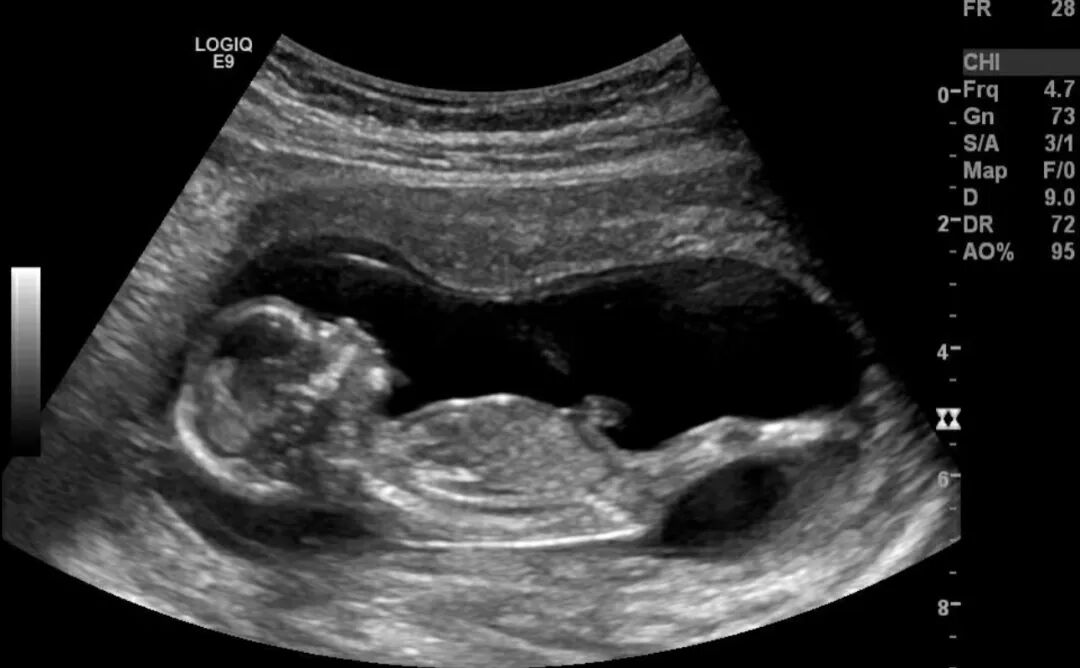

· 孕6-7周: 看是否有胎芽和胎心搏动。看到胎心是第一个重大的胜利里程碑!

· 孕12周左右: 做NT检查(早期唐氏筛查),这是第一次重要的排畸检查。